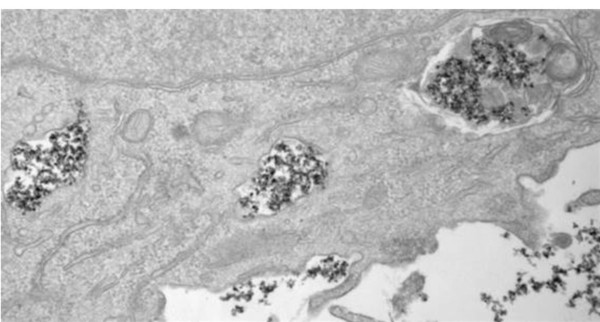

El estudio ha observado que en las células tumorales de modelos de ratón, las nanopartículas se acumulan en endolisosomas, donde se degradan más lentamente, mientras que en las células macrofágicas que envuelven al tumor, la degradación tiene lugar con más o menos rapidez según sea el recubrimiento.